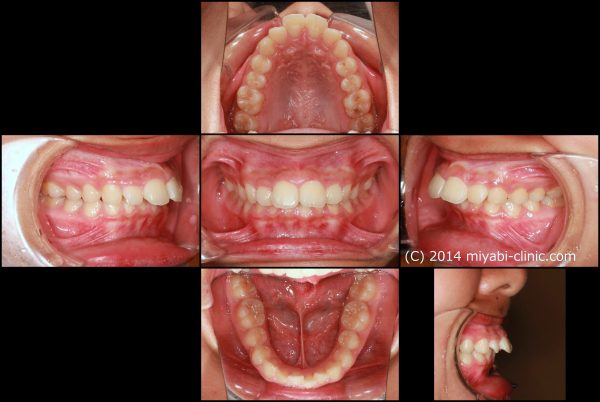

前歯が 飛び出しています。 典型的な ”出っ歯” の状態です

前歯 2本がより前に飛び出ていることが見た目をより悪くしています

前歯が 強く傾斜して、骨ごと 前に 出ています

上顎前突症(いわゆる 出っ歯)です

叢生を伴う 上顎前突症です

口もとの出っ張り、 前歯を下げるために上下顎左右の小臼歯抜歯を行い、前歯を後方に移動させました。

2023年7月15日にスタートして、2025年4月7日に終了しました。

治療期間は22か月でした。